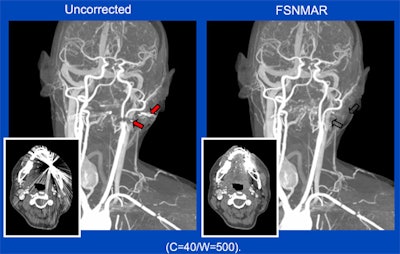

"With PET/MRI, we currently see the implementation of bone tissue in the head region by using ultrashort echo time sequences, the addition of bones in the body by using atlas-based methods, the correction of truncation artifacts using new sequences that are able to extend the MR imaging field-of-view (HUGE), the correction of motion artifacts in thorax and liver imaging, and finally, the reduction of metal artifacts around implants using appropriate metal artifact reduction sequences," Quick stated.

In addition, obesity and metal prostheses also can constrain MR field-of-view. Hip implants, for example, are known to create large-volume artifacts and signal voids in MR images that could affect diagnostic assessments of surrounding tissues, he explained.